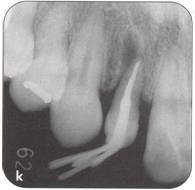

Fi 545e45f g 5-3j After transplantation. Fi 545e45f g 5-3k Three months after transplantation. Because healing of the pulp was not achieved, apexification was initiated. |

Fi 545e45f g 5-3h The extracted donor tooth. The form of the root and the amount of the periodontal ligament are not ideal. Fi 545e45f g 5-3i Suture of the gingival flap and fixation after transplantation. |